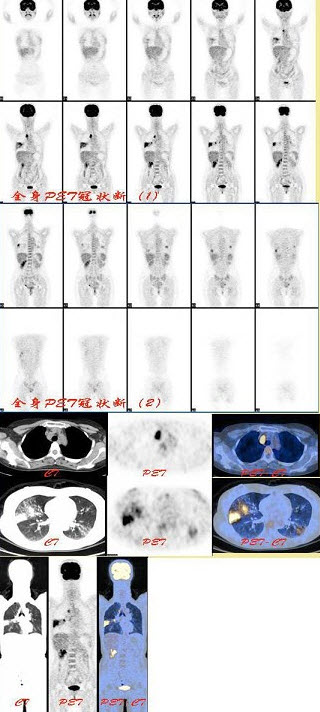

187、多项选择题

男,68岁,肺癌术后半年,诉双下肢疼痛3个月,行全身骨显像如图,可能的诊断是()

A.双侧下肢骨骨转移瘤

B.热髌征存在

C.广泛骨转移瘤

D.双下肢肥大性骨关节病

E.以上都不是